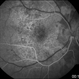

Syphilis Placoid Epitheliopathy

50-year-old patient, syphilis placoid epitheliopathy.